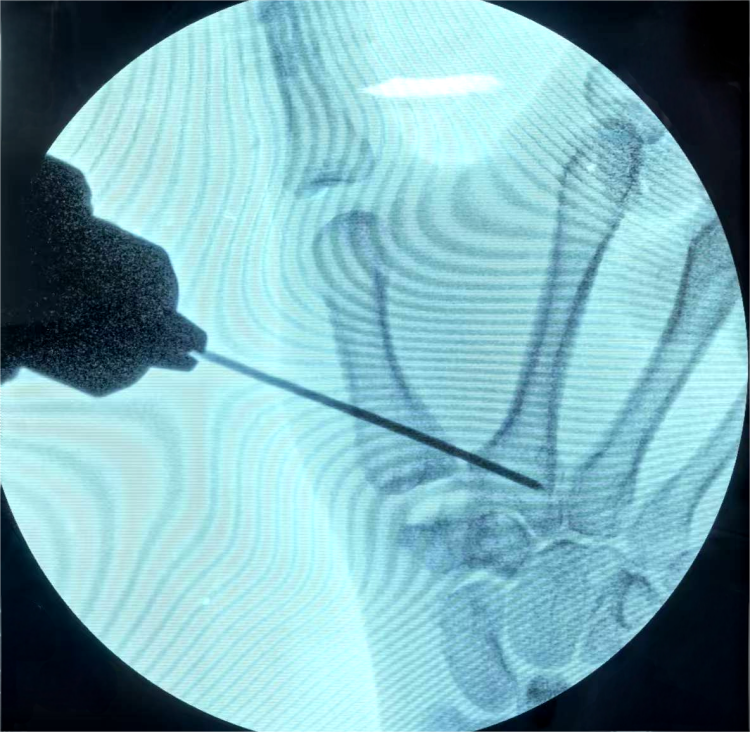

为给患者制定最优治疗方案,张诚主任带领科室医务人员对患者病情进行了全面深入评估,充分结合科室在腕关节镜微创领域的长期技术积淀,最终为患者量身定制了“关节镜下第一腕掌关节成形+第一掌骨克氏针固定悬吊+关节囊皱缩”的微创治疗方案。

手术由医院手外科、足踝外科主任医师张诚主刀,副主任医师盖茂杨协助完成。术中仅通过关节两侧各约3毫米的微小切口,借助关节镜精准探查并完成全部操作,整个手术历时仅不到一小时就顺利结束。这种微创术式不仅最大限度减轻了手术创伤,更精准保留了拇指关键功能,契合患者对高质量术后恢复的需求。目前,患者恢复良好,已顺利出院,逐步回归正常生活。